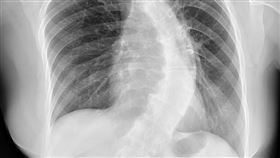

婦人脊椎側彎120度難手術

臨床上一名60歲的婦人自年輕時就有脊椎側彎,由於長期...

2021/02/22 22:00